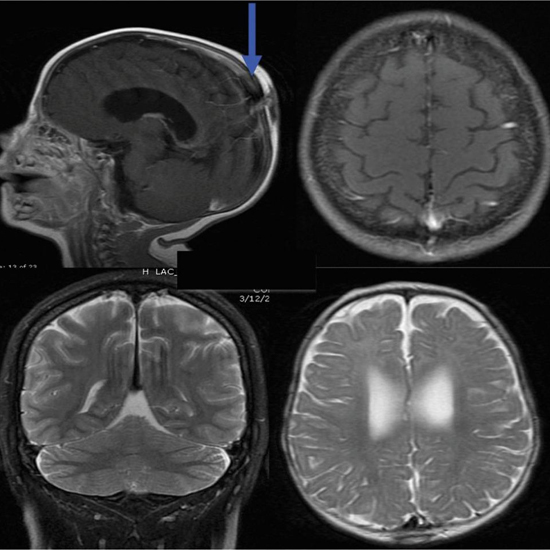

Програма для морфометричного аналізу при МРТ-скануванні головного мозку AI-Rad Companion Brain MR for Morphometry Analysis автоматично сегментує мозок на МРТ-знімках, вимірює його обсяг і зазначає відхилення від норми. Програма AI-Rad Companion Prostate MR for Biopsy Support автоматично сегментує передміхурову залозу на МРТ-знімках і дозволяє лікарям відзначати осередки уражень, роблячи процес біопсії передміхурової залози більш цілеспрямованим.

AI-Rad Companion Brain MR for Morphometry Analysis забезпечує волюметрію головного мозку, яка включає вимір сірої та білої речовин і спинномозкової рідини в різних сегментах мозку, а також порівняння отриманих результатів з нормою. Програма здатна автоматично ідентифікувати близько 30 сегментів мозку на МРТ-знімках, вимірювати їх обсяги та порівнювати результати. У разі типової клінічної картини зниження обсягів може означати наявність хвороби Паркінсона, Альцгеймера чи інших форм деменції. Раніше сегментацію та порівняння з показниками норми проводили вручну або напівавтоматично.